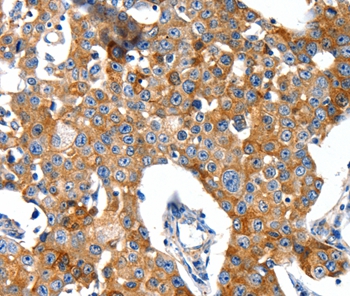

Immunohistochemical analysis of paraffin-embedded Human gastric cancer tissue using #37006 at dilution 1/40.

Immunohistochemical analysis of paraffin-embedded Human breast cancer tissue using #37006 at dilution 1/40.